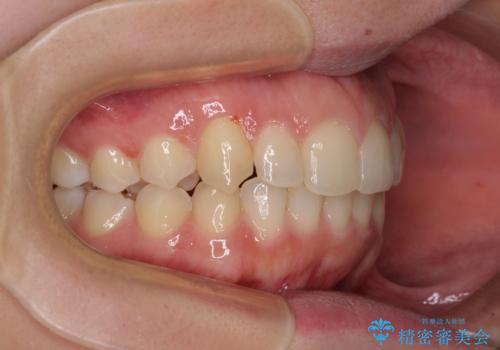

骨格的に左右にずれいている 前歯のデコボコをインビザラインで解消

- 前歯のデコボコと八重歯を気にして来院された患者様です。

叢生の程度は中等度であったため、IPR(歯と歯の間を削る)と歯列の側方拡大をメインに、インビザラインを用いて歯列を改善することとしました。

また、下顎骨の右側変位による右側臼歯の咬合を改善させるよう試みることとしました。

右側の咬合改善を目標に様々な手法を用いましたが、骨格的なズレによる不正咬合はインビザラインでは改善することができませんでした。